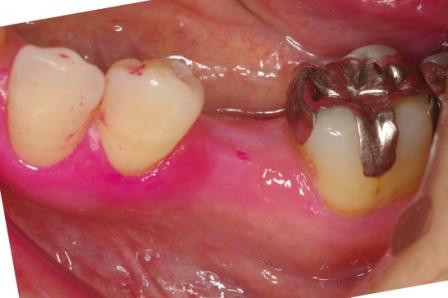

インプラント(人工の歯根)を入れた症例です。

歯の根っこにひびが入り、抜歯となった左下にインプラント(人工の歯根)を使って歯を入れました

前後の歯を削らずにすみます